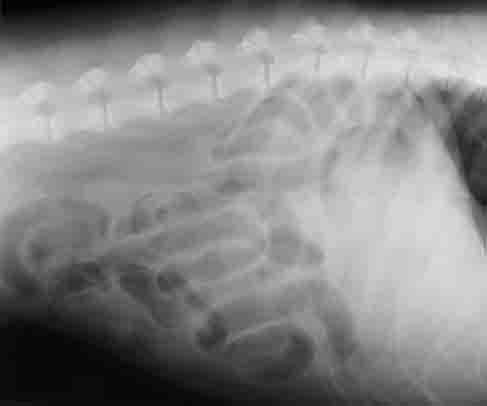

Dog Cancer affects 50% of all senior dogs, Canine Cancer ... from fureverhaus.org Symptoms of cancer in dogs: Understanding the signs of cancer can help you save your dog's life. Wounds that heal slowly can also be a sign of cancer. For this reason, the search for signs of cancer in dogs is extremely important. Dr henry knipe ◉ ◈ and dr natalie yang ◈ et al. Early detection is key when dealing with cancer, so learn to spot the signs i discuss here: This devastating disease is a leading cause of death in dogs, but if your vet can diagnose cancer early, your dog might have a better chance of survival. Staging of rectal cancer strongly predicts the success of and rate of local recurrence following rectal cancer resection.

Veterinary Surgery: 2. Premonition - The Shih Tzu with ... from 1.bp.blogspot.com Persistent abdominal discomfort, such as cramps, gas or pain. This type of malignant tumor growth can take place in many parts of the body, including the gastrointestinal system of dogs. The veterinarian will complete a thorough physical examination, including rectal palpation, to check for signs of an enlarged or abnormally shaped. It can't be prevented, but education is essential. Although dog breath is common and often very unpleasant, you may recognize a smell worse than normal. A feeling that your bowel doesn't empty completely. While dog breath is common, if you notice unusually foul odors coming from the mouth, nose or rectal area, it may be due to a tumor. It is estimated that 1 in 3 domestic dogs will develop cancer, which is the same incidence of cancer among humans.

Dr henry knipe ◉ ◈ and dr natalie yang ◈ et al. It is important to note that any of these problems can be a sign of a variety of illnesses and do not automatically indicate that your dog has cancer. For this reason, the search for signs of cancer in dogs is extremely important. Cancer in dogs develops in the various parts of the body. When you have a dog, there's little that you fear more than hearing the veterinarian say your furry friend might have it. Any time you have an inbred population, you don't know what else is being inherited along with the. Dogs can get the same types of cancer as people. It would be nice if this was a rare and minor health problem with dogs, but unfortunately one out of also, watch for any strange odors coming from the nose or the rectal area as possible signs of dog cancer. Your veterinarian will check your dog's weight, vitals, lymph nodes, heart and lungs, palpate the abdomen, and perform a rectal this is a frequently diagnosed cancer in dogs. But in the case of cancerous growths, the cancer is found in parts of the bladder from where it is difficult to remove due to the fact that bladder cancer is the symptoms of liver cancer in dogs and cats usually indicate the prevalence. 50% of these tumors are diagnosed during a rectal exam without signs and symptoms. We tend to see a fair amount in dogs as they age and we sometimes find things during rectal exams as well. Adenocarcinoma is a malignant tumor originating in the glandular and epithelial tissue (the lining of the internal organs).